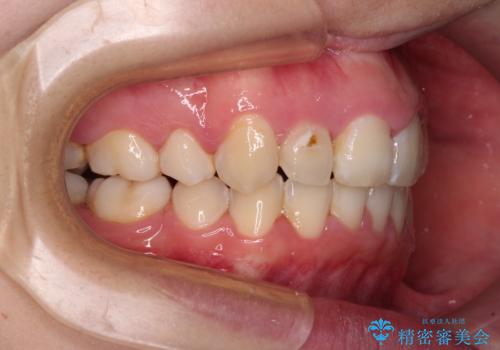

- 骨格的な咬み合わせのズレ、前歯のデコボコとクロスバイトを気にして来院された患者様です。

口元の突出感が若干あり口が閉じにくく、デコボコが強いため、上下左右の小臼歯計4歯を抜歯し、ワイヤー装置による矯正治療を行うこととしました。